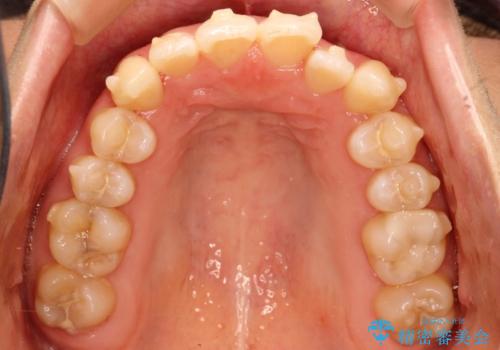

初診時の歯並びの状態としては、上下ともに全体に及ぶの中等度以上のがたつき(叢生)があり、前歯数本が反対交合の状態でした。

強い叢生がありましたが、抜歯は行わず上下顎ともに、主に歯列弓の拡大とディスキング(歯と歯の間に隙間を作る処置)を行い叢生を改善しました。

見た目、嚙み合わせ及び、治療期間や施術内容に大変ご満足いただきました。